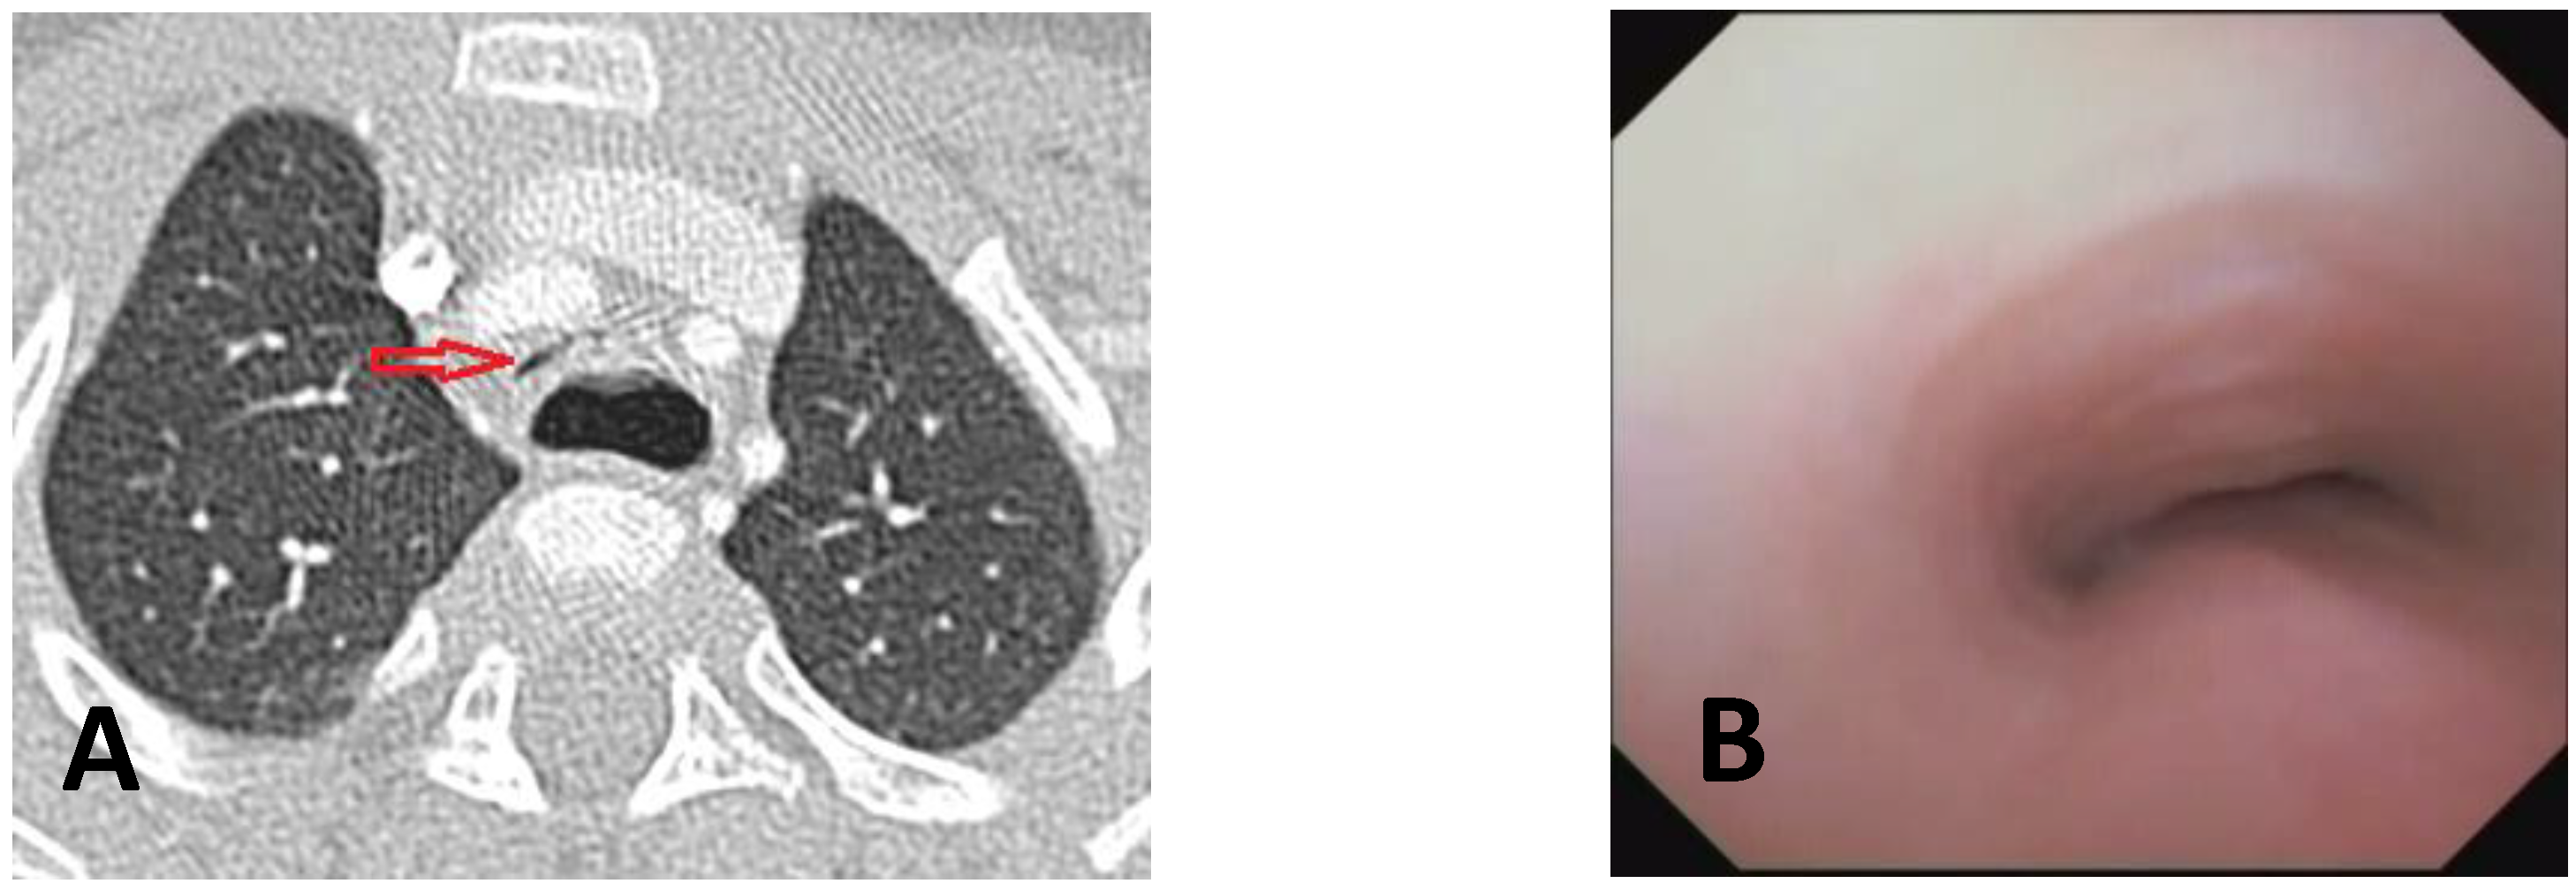

- Computed Tomography (CT): This is a continuously evolving imaging technique, rapid and non-invasive, providing an excellent overall view, independent of body size, with high spatial/temporal resolution. It allows multiplanar and volumetric reconstructions (MPR, MinPR, MipPR, and Volumetric 3D). It can be performed on children of all ages; anesthesia/sedation may be necessary under 5 years of age. Flash Monophasic Technique performed with a single scan, after intravenous injection of CM, provides information on airway morphology (but not dynamics), visualizing airways even distal to the site of obstructions and on mediastinal vessels exerting compression on the trachea or bronchi, highlighting any mediastinal pathology. CT shows cardiovascular anomalies compressing the airway, such as right aortic arch, complete/incomplete double aortic arch, pulmonary sling, and aberrant IA, all causing more or less severe TBM [16]. TM is very frequently associated with EA; CT can demonstrate malacia and extrinsic tracheal compression with a significant reduction in the tracheal ADP at the point of intersection with IA. CT can also demonstrate irreversible lung damage, such as bronchiectasis formation, caused by chronic recurrent lung infections resulting from reduced mucociliary clearance in TBM. Skeletal anomalies (e.g., pectus excavatum and scoliosis) that can cause airway compression and consequent TBM are also demonstrated. CT also evaluates tracheal compressions caused by space-occupying mediastinal lesions. Virtual bronchoscopy obtained with 3D airway reconstruction on CT images has not been very sensitive (<75%) in detecting TBM [17,18].